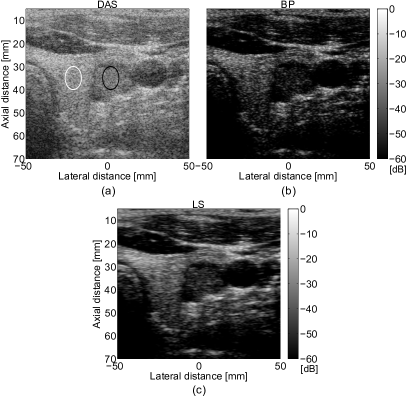

Figure 10: (a) DAS, (b) BP, and (c) LS BF results of in vivo helthy thyroid data.

Fig. 10 presents the beamforming results of healthy thyroid data. The thyroid (echoic region) is situated between the trachea and the carotid artery (laterally, between -20 mm and 30 mm approximately). Fig. 10 (a) illustrates the result obtained with DAS BF. As expected, the contrast of the image is low and it is hard to distinguish the thyroid structure from the trachea, especially in the upper-left part of the thyroid. However, when BP (Fig. 10 (b)) and LS Fig. 10 (c) are used, the thyroid region is easy to be identified, and the contrast of the image is increased.

TABLE V: CNR, SNR, and RG values for the in vivo healthy thyroidal beamformed images from Fig. 10

BF Method CNR SNR RG

DAS 0.55 0.22 1

BP 1.13 0.32 3

LS 1.56 0.64 2.5

The values of CNR, SNR, and RG are depicted in the Table V. To compute CNR we considered region R2subscript𝑅2R_{2} inside the thyroid (the black circle positioned at approximately 1010-10 mm laterally), and the region R1subscript𝑅1R_{1} inside trachea (the white circle positioned at approximately 4040-40 mm laterally). The SNR for R1subscript𝑅1R_{1} was computed. We can observe that the best values of the CNR and SNR are obtained when LS method was applied, the thyroid region being obvious to be discerned. The boundaries of the carotid artery are also well defined, Fig. 10 (c).